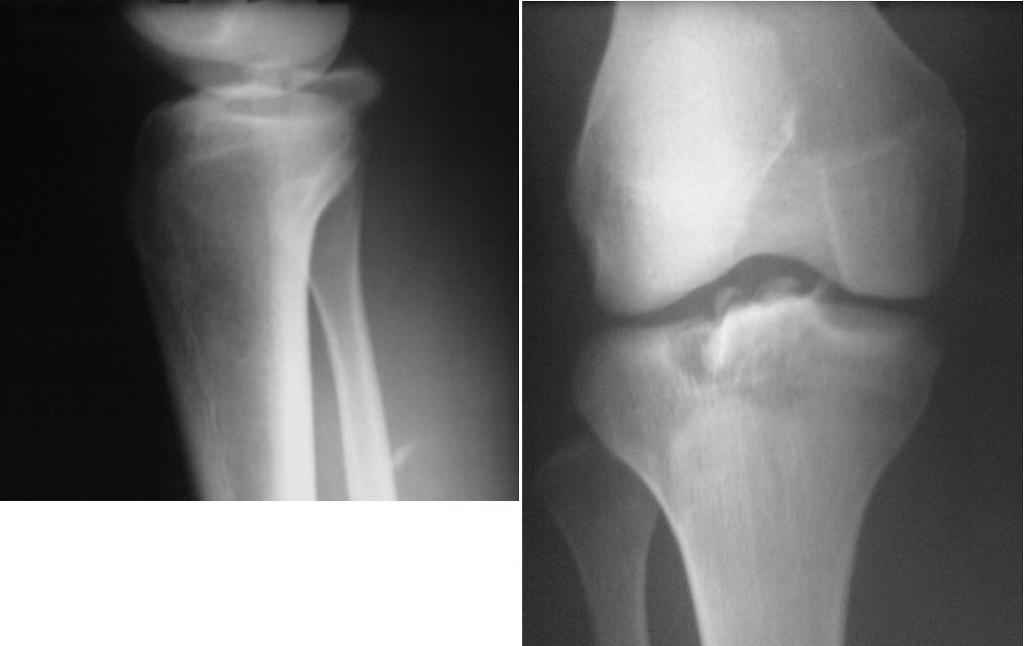

перелом межмыщелкового возвышения, нужен совет по лечению

перелом межмыщелкового возвышения, у больной 15 лет. посоветуйте что можно предпринять.

Алексей, если есть возможность, сделайте КТ. Результаты можно посмотреть и обсудить. Если КТ нет - проведите консервативно. Объясню почему: смещение отломков по рентгенограммам незначительное, сделайте пункцию сустава, промойте анестетиком, разогните максимально и наложите гипсовую повязку.

КТ мы конечно сделали, судя по результатам смещение довольно большое и оставить его без репозиции не представляется нам возможным. Планируем артротомию задним доступом и фиксацию фрагмента винтом или проволочным швом. Артроскопа не имеем.

Это чрезкостный разрыв задней крестообразной связки (отрыв этой связки с костным фрагментом). Будте готовы к пластике ЗКС, если не сможете натянуть связку. Двумя доступами. Если придется брать трансплантат связки - смотрите, что привыкли, но только не исскуственный материал!

Алексей, с КТ - совсем другая история. Артроскопия здесь не поможет. И согласен с Вашим планом. Имею опыт лечения таких больных. Мы делали артротомию задним срединным доступом, репонировали отломки и фиксировали проволочной петлей, выводя ее на переднюю поверхность голени, где и "закручивали" ее. Результаты, простите, очень хорошие: полный объем движений и никакой нестабильности. Удаление проволоки из переднего доступа на голени - без технических проблем.